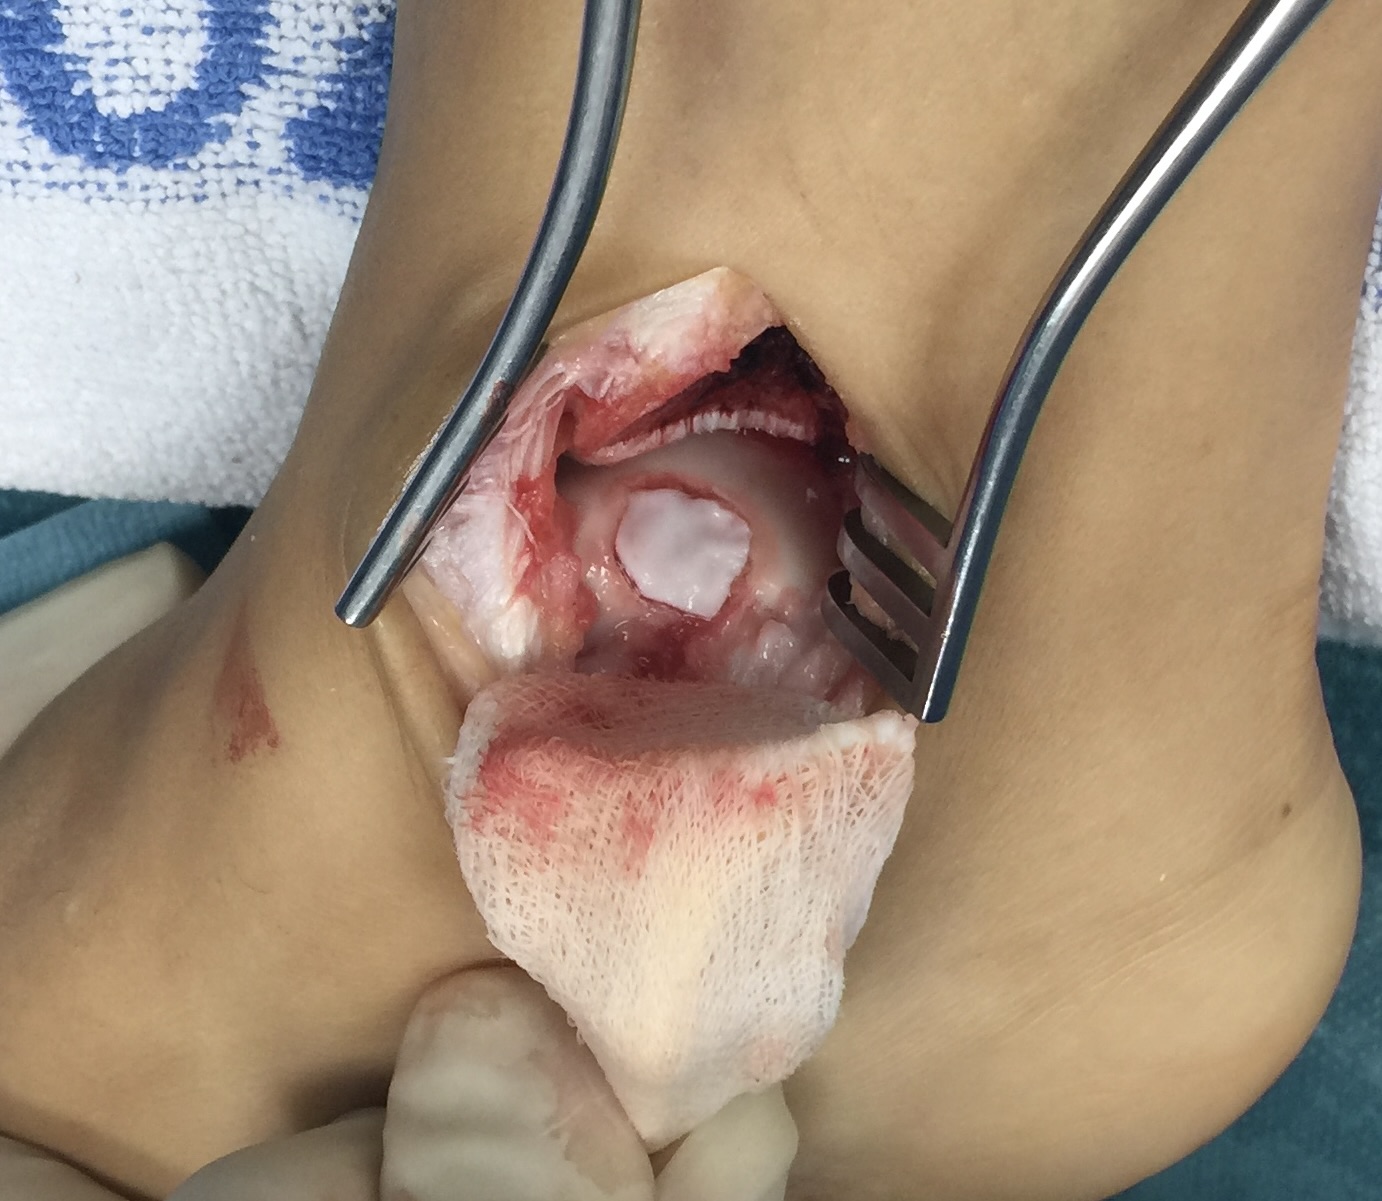

Lesiones osteocondrales

Las lesiones osteocondrales son las que afectan al cartílago y hueso de las articulaciones.

Son frecuentes y especialmente graves las que afectan al astrágalo ya que el cartílago no tiene capacidad por sí mismo de regeneración.

La causa generalmente suele ser un traumatismo aunque muchas veces no es importante, pudiendo desencadenarse por microtraumatismos repetidos (torceduras, esguinces, etc.).

El paciente suele referir dolor en el tobillo, a veces con inflamación y con sensación de fallo o poca estabilidad. Para el diagnóstico es imprescindible una minuciosa exploración, ya que en muchas ocasiones existen factores biomecánicos favorecedores de esta patología, como son alteraciones en el eje del pie o la pierna o inestabilidades por fallo de los ligamentos. El diagnóstico clínico deberá correlacionarse con exámenes radiológicos, de resonancia magnética y/o TAC para aconsejar y planificar el tratamiento más adecuado según cada caso.

Existen diversas técnicas para el tratamiento de la lesión osteocondral, desde la reparación mediante estimulación ósea por microperforaciones, a la aplicación de técnicas avanzadas de regeneración mediante cultivo de condrocitos o de sustitución mediante injerto osteocondral. La indicación de cada una debe ser individualizada según el paciente, la edad, el tamaño y profundidad de la lesión. En ocasiones deberá corregirse además la existencia de una alteración en el eje de apoyo del pie o la reparación ligamentaria.

En nuestra consulta le ofreceremos un enfoque completo, en el tratamiento de estas lesiones y en la indicación de las técnicas más precisas según cada caso.